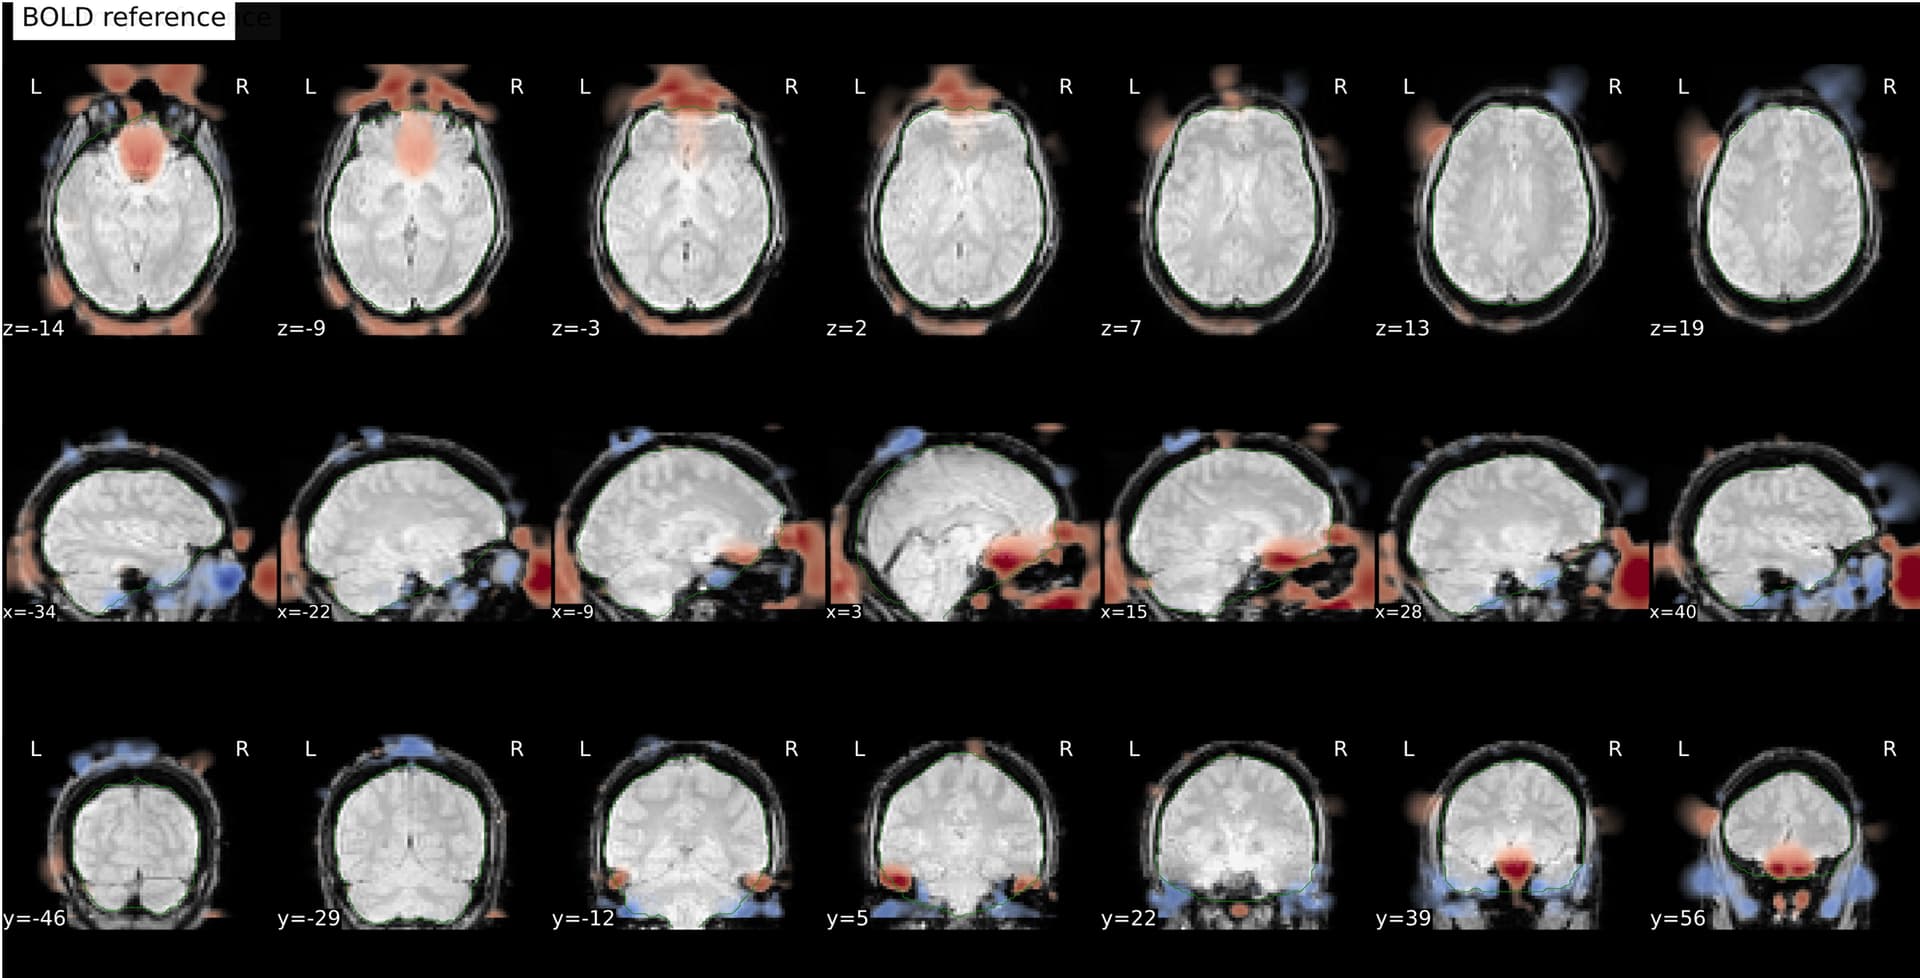

I’m seeing an apparent misalignment in the fmapCoreg reportlet for a PEPOLAR (SE-EPI AP/PA) distortion-correction workflow

- The SDC before/after panel looks okay-ish, suggesting distortion correction itself is likely working somehow, but poor than for subjects where fmap-bold coreg works as expected.